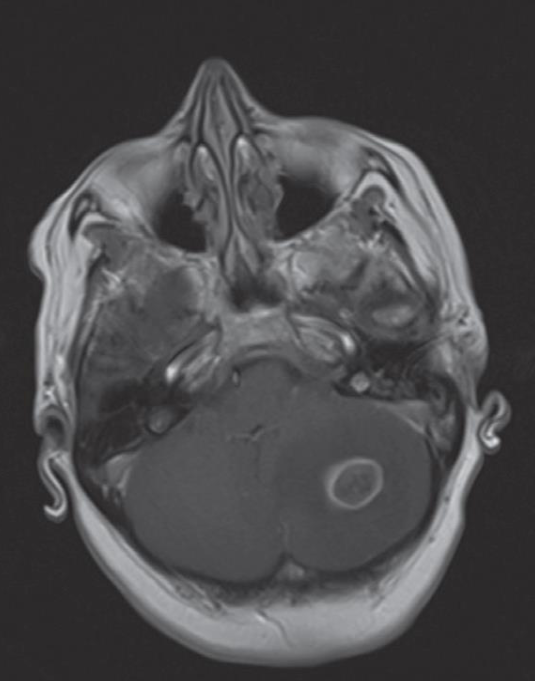

A. Give the name of the pattern of contrast enhancement of the lesion in the given image

- Enhanced axial T1 weighted MRI scan

- ring-enhancing cerebellar metastasis

B. Give ONE cause for the pattern of contrast enhancement shown in the given image Metastatic brain tumors